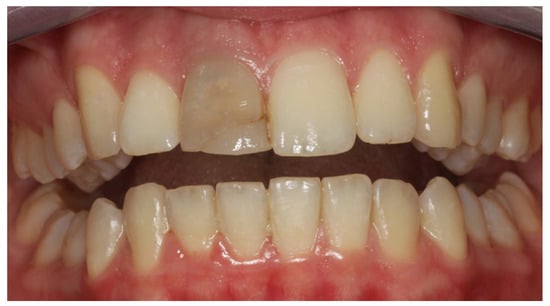

2. Clinical Case